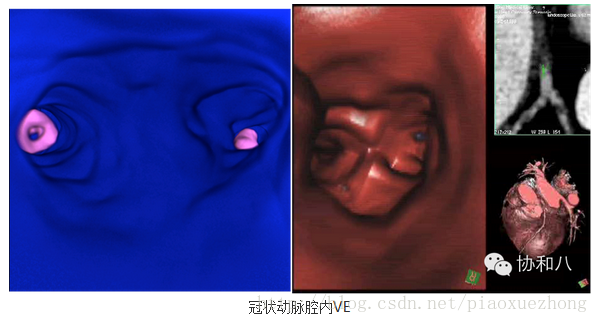

虚拟内镜技术(VE)

这种CT重建图像可以模拟各种内镜检查的效果,它是假设视线位于索要观察的管“腔”内,通过设定一系列的参数范围,即可看到管“腔”内的结构: